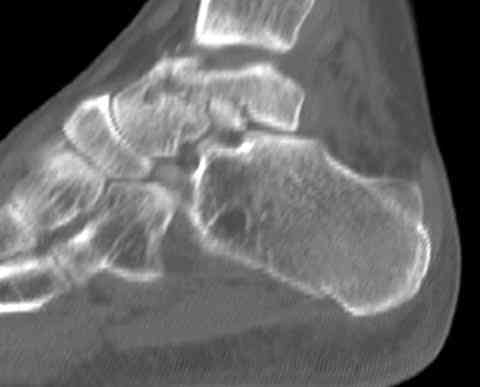

Случай с множественным оскольчатым переломом тарана оперированный из двойного доступа.

Через 2 мес.:

Через 8 мес.:

Через 14 мес.: